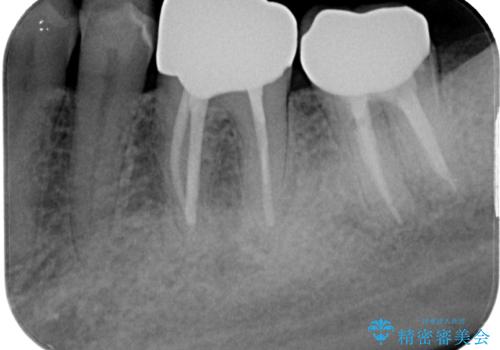

下顎大臼歯の再根管治療とオールセラミッククラウンによる補綴治療

根管治療後は痛みもなくなりました。

強い咬合力による歯根破折を予防するためにナイトガードの使用も有効です。